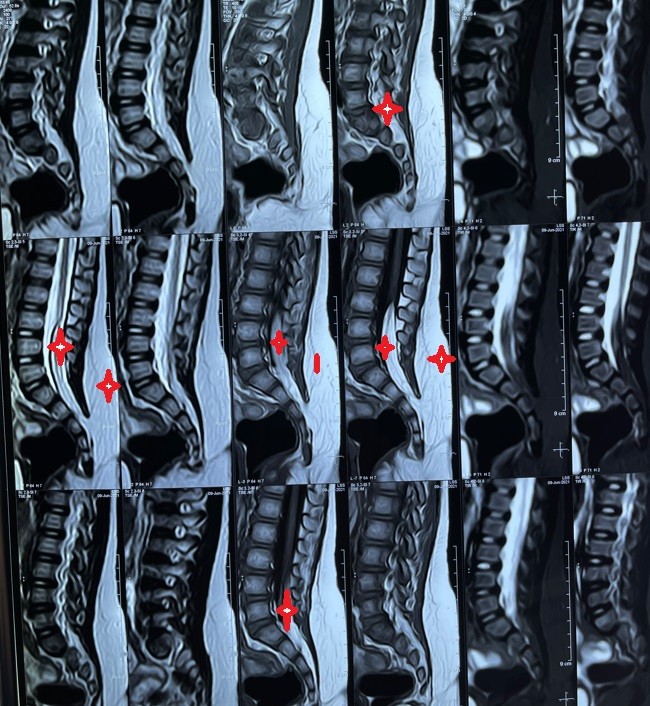

ورم دهني خلقي بالفقرات القطنيىة

ورم دهني خلقي بالفقرات القطنية

صور من اجراء جراحة لطفلة عامان تعاني من بروز جانبي اسفل الظهر سببه ورم دهني متصل بكيس الاعصاب بالفقرات القطنية و العجزية